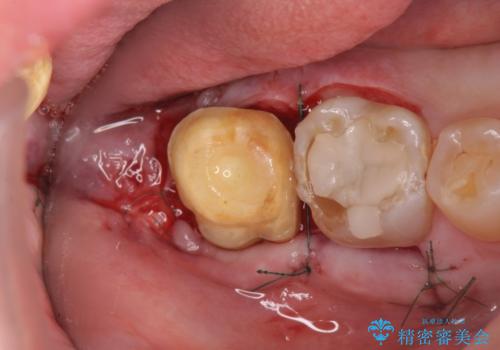

歯ぎしりによる異常に低い歯冠高径 歯周外科による解決

失活歯であるため根管治療ののちクラウン製作が治療計画として考えられますが長年のすり減りによりクラウン高径がほとんどなくてなってしまっている状態です。

歯周外科を行い歯茎の位置を下げることで安定したクラウン製作ができる状態を目指します。

あまりにもクラウン高径が低いと、安定性が悪くなりセメントの溢出を招き虫歯の再発リスクを高めます。